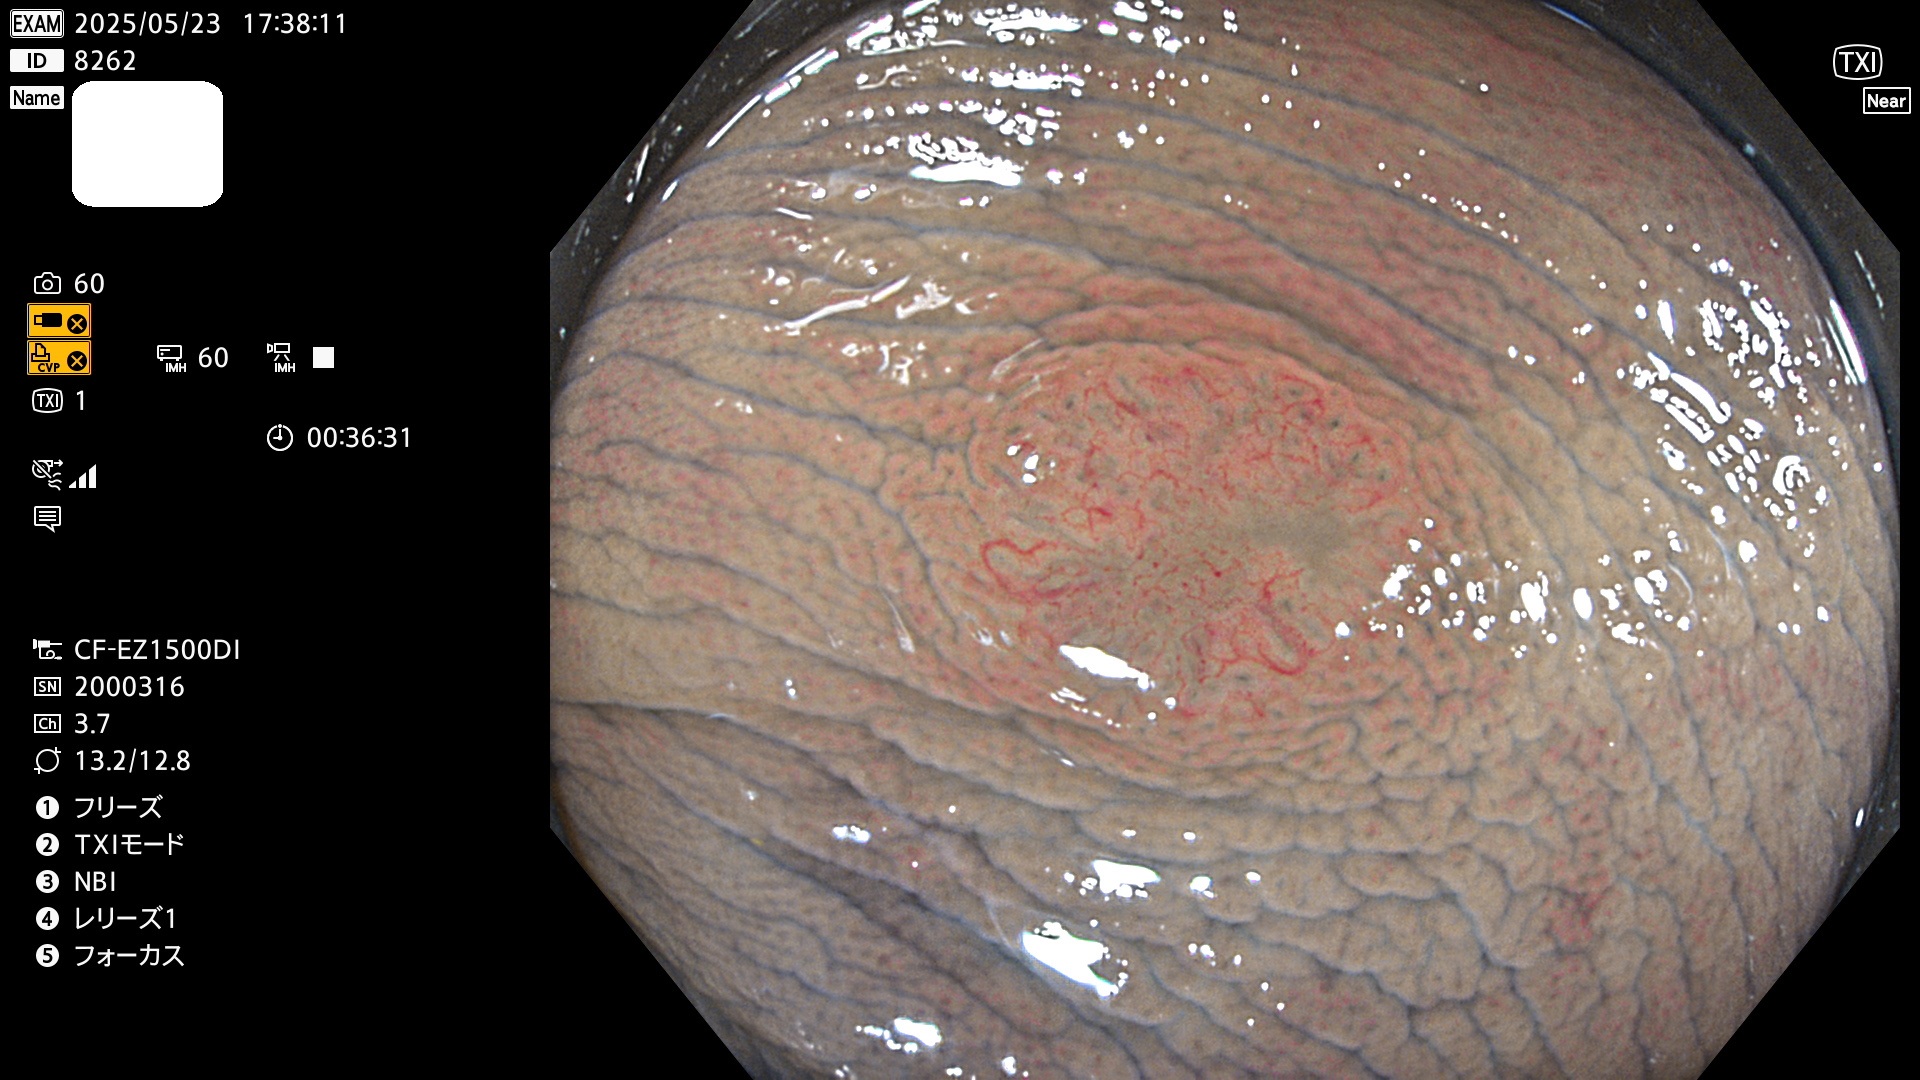

今週のUb、Uc型腺腫

完全に平坦な物をUb、陥凹している物をUcと呼びます。Ubは認識が困難で、Ucはびらん(炎症)と紛らわしいために見落とされやすく、「内視鏡後・大腸癌」の原因になります。

毎週の検査(木・金・土・日)に発見されたUb、Uc型・腺腫を、その週の日曜の夜にUPし1週間、提示します。

抽出の対象期間 2025年5月22日〜5月25日の4日間(48件の検査)10個 (10/48=21%)